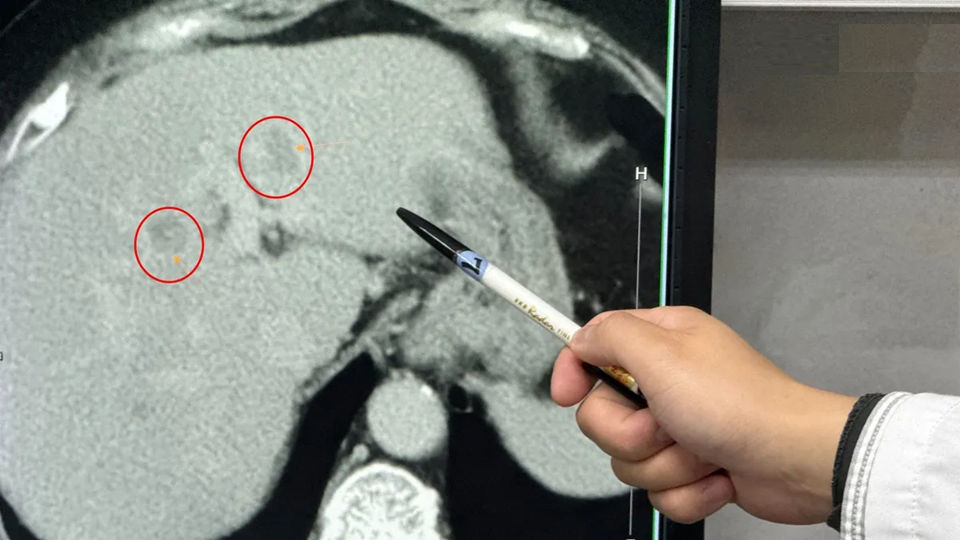

Theo bác sĩ Ngô Khôn Đạt, bác sĩ ngoại tổng quát đang công tác tại Bệnh viện Liên hợp Lý (Đài Loan, Trung Quốc), bệnh nhân nhập viện vì cảm thấy cơ thể mệt mỏi bất thường. Khi siêu âm ổ bụng tại khoa tiêu hóa, các bác sĩ phát hiện gan nhiễm mỡ mức độ nặng kèm theo nghi ngờ có khối u. Kết quả kiểm tra chuyên sâu cho thấy có hai khối u nằm ở thùy ngoài bên trái và phần giữa thùy trái của gan.

Đáng chú ý, tỷ lệ mỡ trong gan của bệnh nhân lên tới 40-60%. Bác sĩ cho biết, ngay cả với người trẻ có gan khỏe mạnh, khi phẫu thuật cắt gan cũng cần bảo tồn ít nhất 1/3 thể tích gan để duy trì chức năng sống. Trong trường hợp này, nếu cắt toàn bộ phần gan trái có khối u, nguy cơ suy gan sau mổ là rất lớn.

Các bác sĩ buộc phải lựa chọn phương án điều trị kết hợp: cắt bỏ 223 gram mô gan nhiễm mỡ nặng, tương đương trọng lượng một quả táo nhỏ, nhằm giảm tải cho gan; các khối u còn lại được xử lý bằng phương pháp đốt sóng cao tần để làm hoại tử tế bào ung thư. Ca phẫu thuật kéo dài hơn 3 giờ, lượng máu mất chỉ khoảng 400ml, bệnh nhân hồi phục tốt sau mổ.